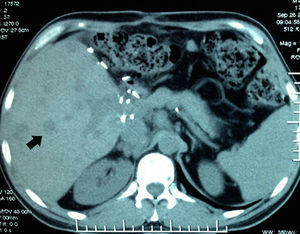

In September the patient presented with haemoptysis and dyspnoea, and was admitted to a private hospital, where a computed tomography (CT) chest scan was indicated (Fig. 2). A bronchoscopy was performed and cultures and biopsies were taken, which tested negative for malignancy, tuberculosis or fungal infection. Plain and contrasted CT scan of the abdomen was indicated which showed multiple, rounded lesions, hypodense in the liver graft (Fig. 3); CT scan-guided biopsy was performed which tested negative to malignancy.

An autopsy was performed, where we observed rounded, vascularised tumours throughout the liver graft, involving the hepatic artery and portal vein (Fig. 4), in pulmonary parenchyma, multiple metastases of small tumours, with bleeding (Fig. 5). Metastasis was also present in the spleen, suprarenal glands and pancreas.